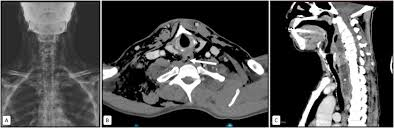

Se usa una amplia gama de técnicas de adquisición de imágenes para poder ver dentro del cuerpo y determinar el alcance de un sarcoma óseo y establecer la presencia o ausencia de enfermedad metastásica distante.

1. Rayos X

2. Resonancia magnética

3. TAC contrastado

4. Gammagrafía Ósea

Las pruebas de diagnóstico por imágenes utilizan ondas sonoras, rayos X, campos magnéticos o sustancias radiactivas para crear imágenes del interior del cuerpo. Las pruebas de diagnóstico por imágenes pueden realizarse por diversos motivos, como:

Las imágenes más representativas o más comunes son:

1. Radiografías de tórax

2. Ultrasonido

3. Tomografía Computarizada

4. PET scan

5. Resonancia Magnética